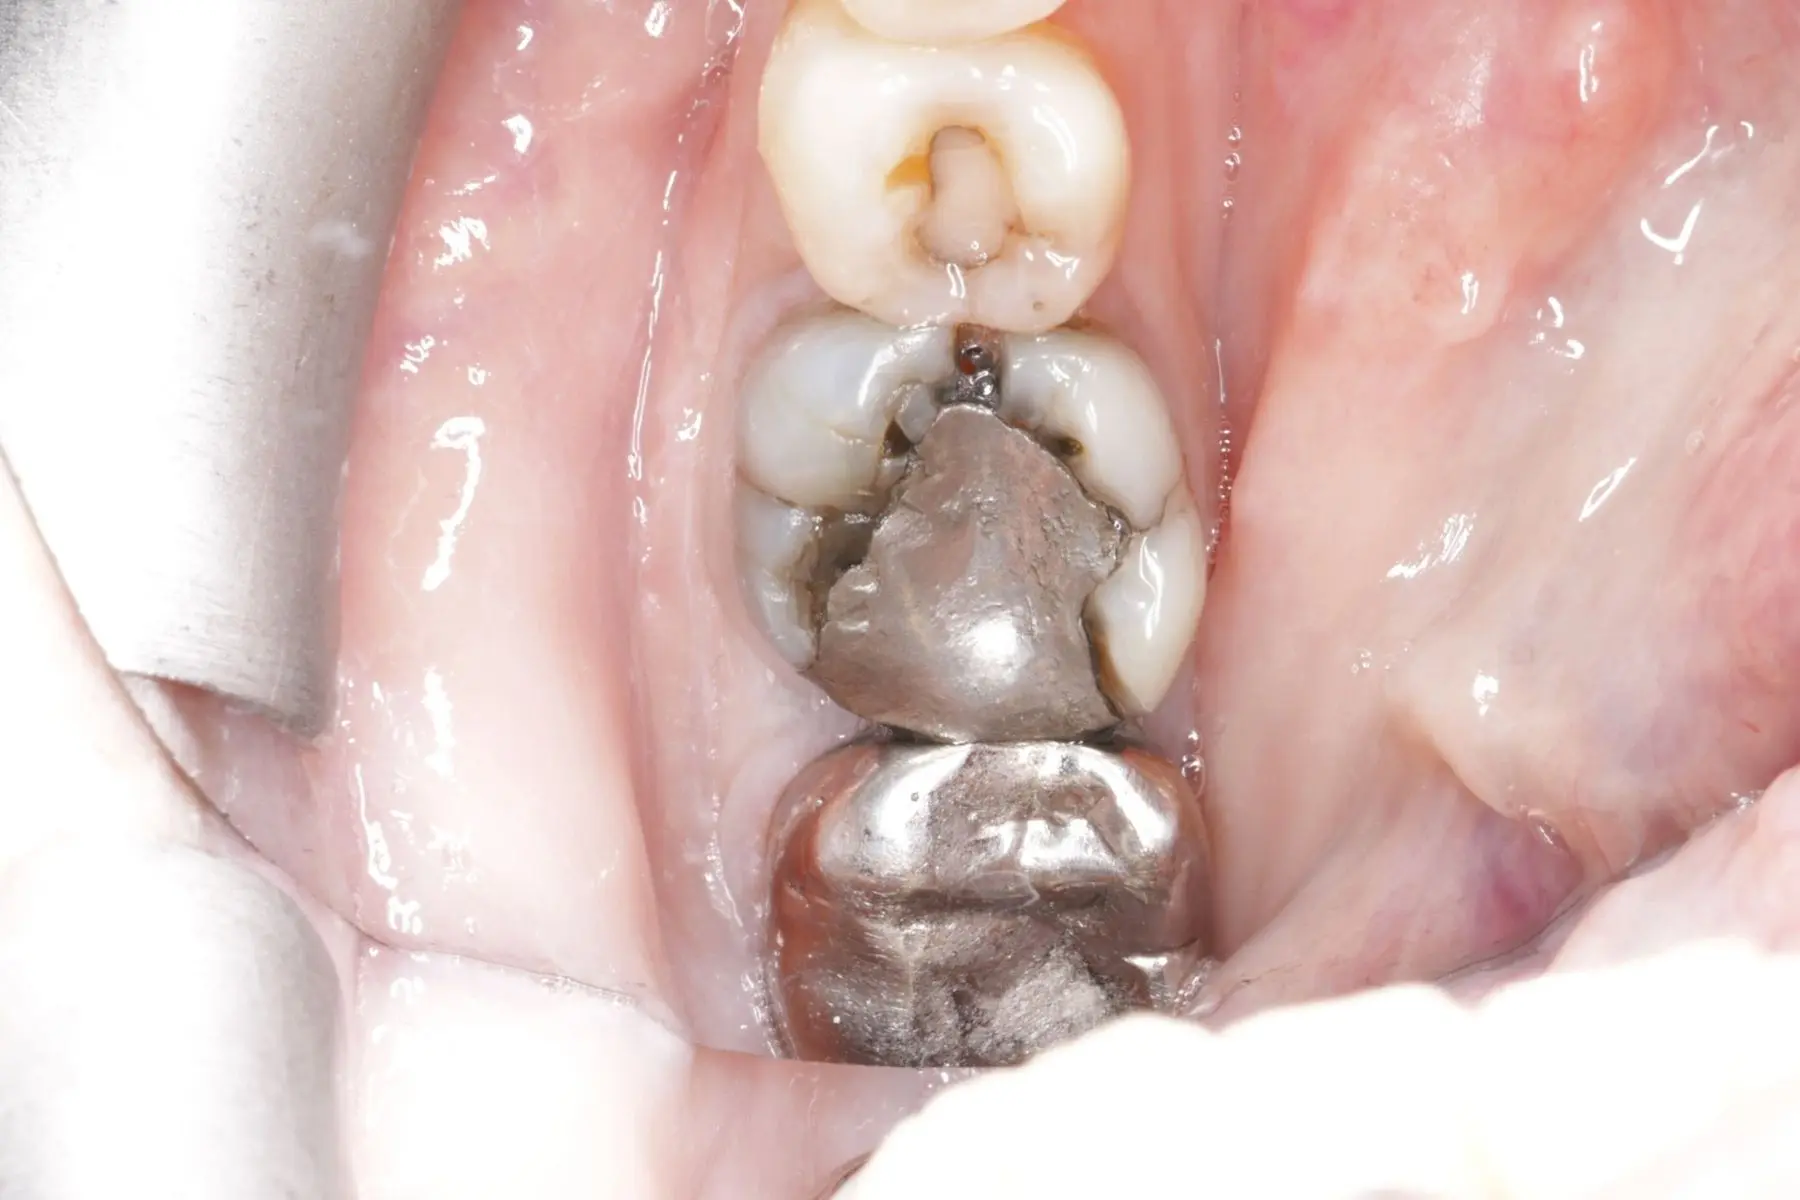

• 術前 34

術後 33

3D齒雕

主治醫師

• 楊明憲

治療時間

約2個月

主訴

左下牙齒痛,想檢查牙齒狀況